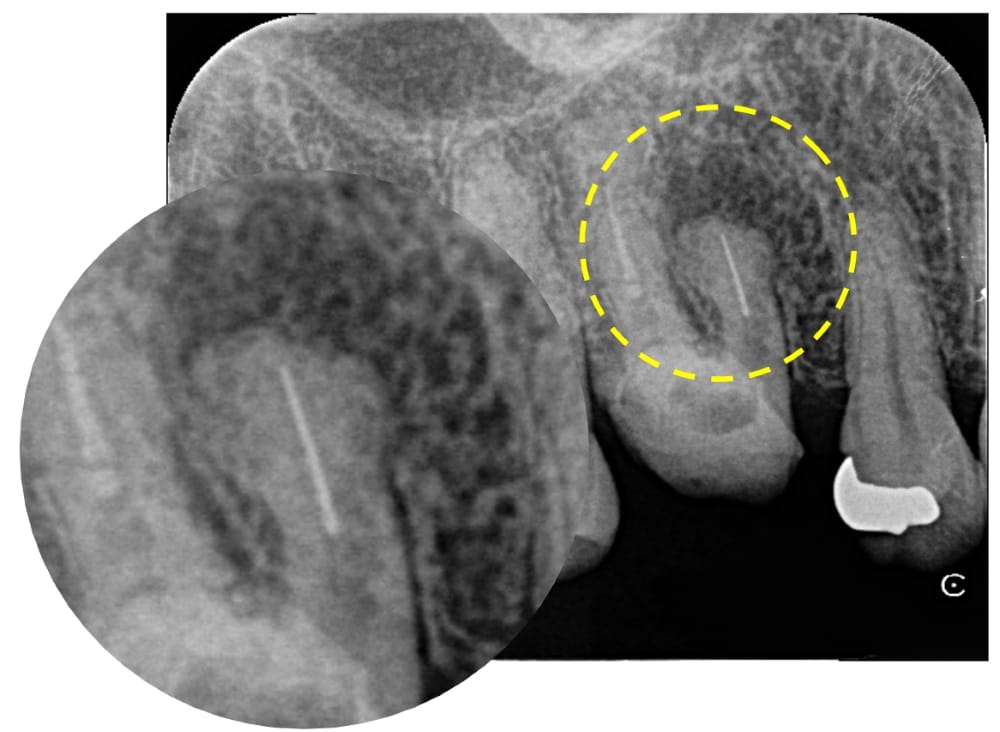

根管内を探索してすぐに、根の中のパーフォレーションが認められました。パーフォレーションとは、歯の本来の根管の方向とは異なる位置に穴があいてしまう偶発症です。おそらく、破折ファイルが起こっていることに気付かぬまま器具操作を行い、根管の中を突き抜けてしまったと推測されます。

(青:本来の根管 黄:パーフォレーション)